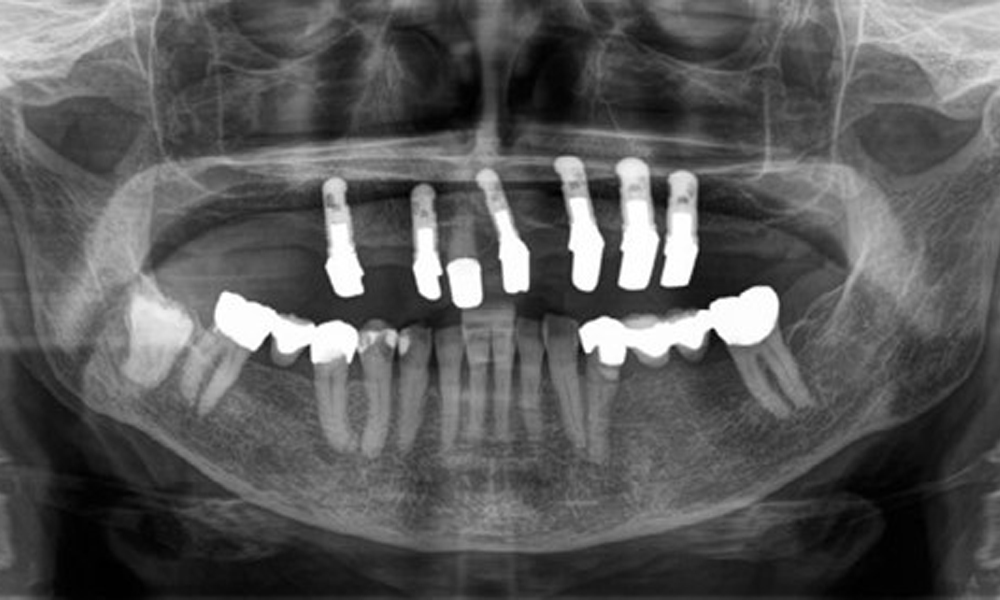

На пациентката е поставена комбинирана подвижна горночелюстна телескопична протеза преди повече от 25 години (фиг. 1, фиг. 2, фиг. 3) и тя е много доволна от протезите си. Пациентката има адекватна фиксирана протеза за долната челюст (фиг. 4).

Денталните открития са следните: Комбинирани снемаеми протези на импланти и телескопични протези, поддържани от зъби, на импланти 15, 13, 21, 23, 24, 25 и зъб 11 (фиг. 1, фиг. 2, фиг. 3). Пациентът е снабден с фиксирана долночелюстна протеза. Над зъби 37-34 и 45-47 бяха налични адекватни мостове (фиг. 4), краищата на коронките бяха интактни и нямаше активен кариес. Върху зъб 43 имаше композитна пломба с маргинална празнина. Имаше рецесия на долната гингива, която разкриваше от 1 до 3 mm от кореновата повърхност. Това се отнася и за 11.

Рентгенологичните резултати показват частично беззъбо съзъбие с горночелюстни импланти за зъби 15, 13, 21, 23, 24, 25 и телескопична коронка на зъб 11. Налице са адекватни долночелюстни мостове, обхващащи участъци от 37 до 34 и от 45 до 47. Зъб 48 е засегнат. Има съмнения за вторичен кариес дистално на 43 и мезиално на 44. 44 е възстановен с нерадиационна облицовка на кухината. Налице е генерализирана хоризонтална костна загуба от приблизително 10-30 % и локализирана вертикална костна загуба, засягаща зъби 22 и 42 (фиг. 5).